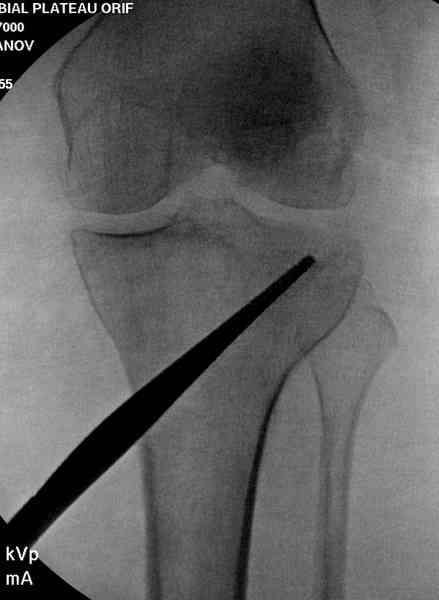

Нет, малоберцовый внизу, фиксацию проводим на верхнем эпифизе, где твердая кость. Задача состоит

в том, чтобы создать арматуру из нескольких проведенных шурупов на эпифизе.

Медиально, обычно на протовоположной

строне, делается окно в кортикальном слое, кривым забойником под рентгеном поднимается импрессия.

Это техника применяется, когда имеется

центральная импрессия, а при ипрессии с краевым переломом - после приподнимания импрессии опорная (Butress) пластина, как на снимке.